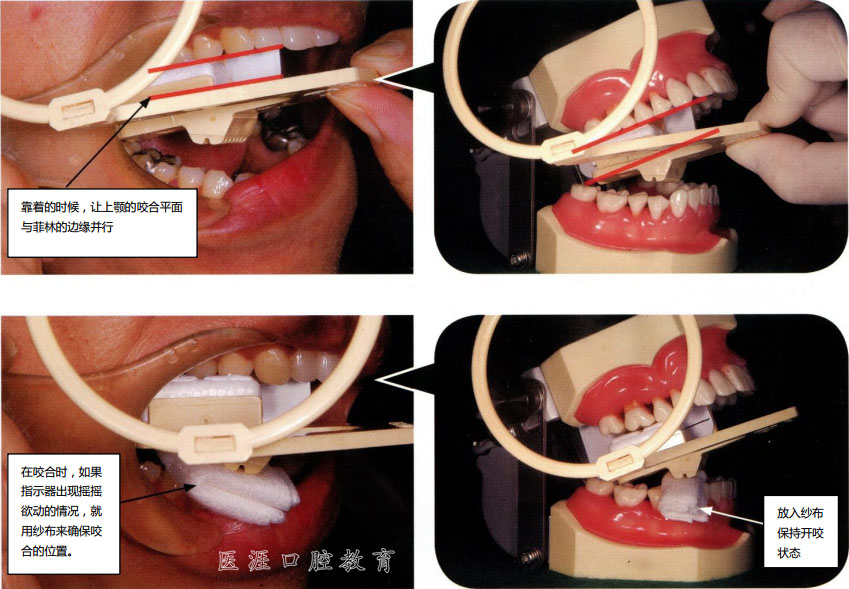

設(shè)置時讓咬合面和菲林邊緣平行

使用指示器拍攝的話可以更簡單地得到規(guī)范的照片,也適用于觀察過程。但是,口比較小的患者或者開口度低的患者要用的話就要花點心思

根據(jù)牙齒的長度和想要看到的部分不同而不同,以離邊緣5~8mm 左右的部分為基準(zhǔn)畫上記號,在附近做好讓先端放過來的定位。

前牙區(qū) 后牙區(qū)